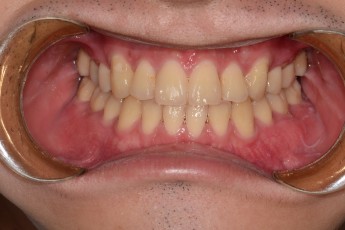

BEFORE & AFTER

- 덧니교정

- 매복치교정